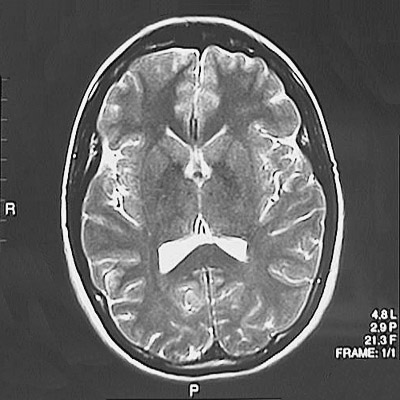

This is a normal axial T2 weighted MRI scan demonstrating the frontal lobe and parietal lobe and occipital lobe and splenium of corpus callosum and caudate and putamen and globus pallidus and thalamus and internal capsule.